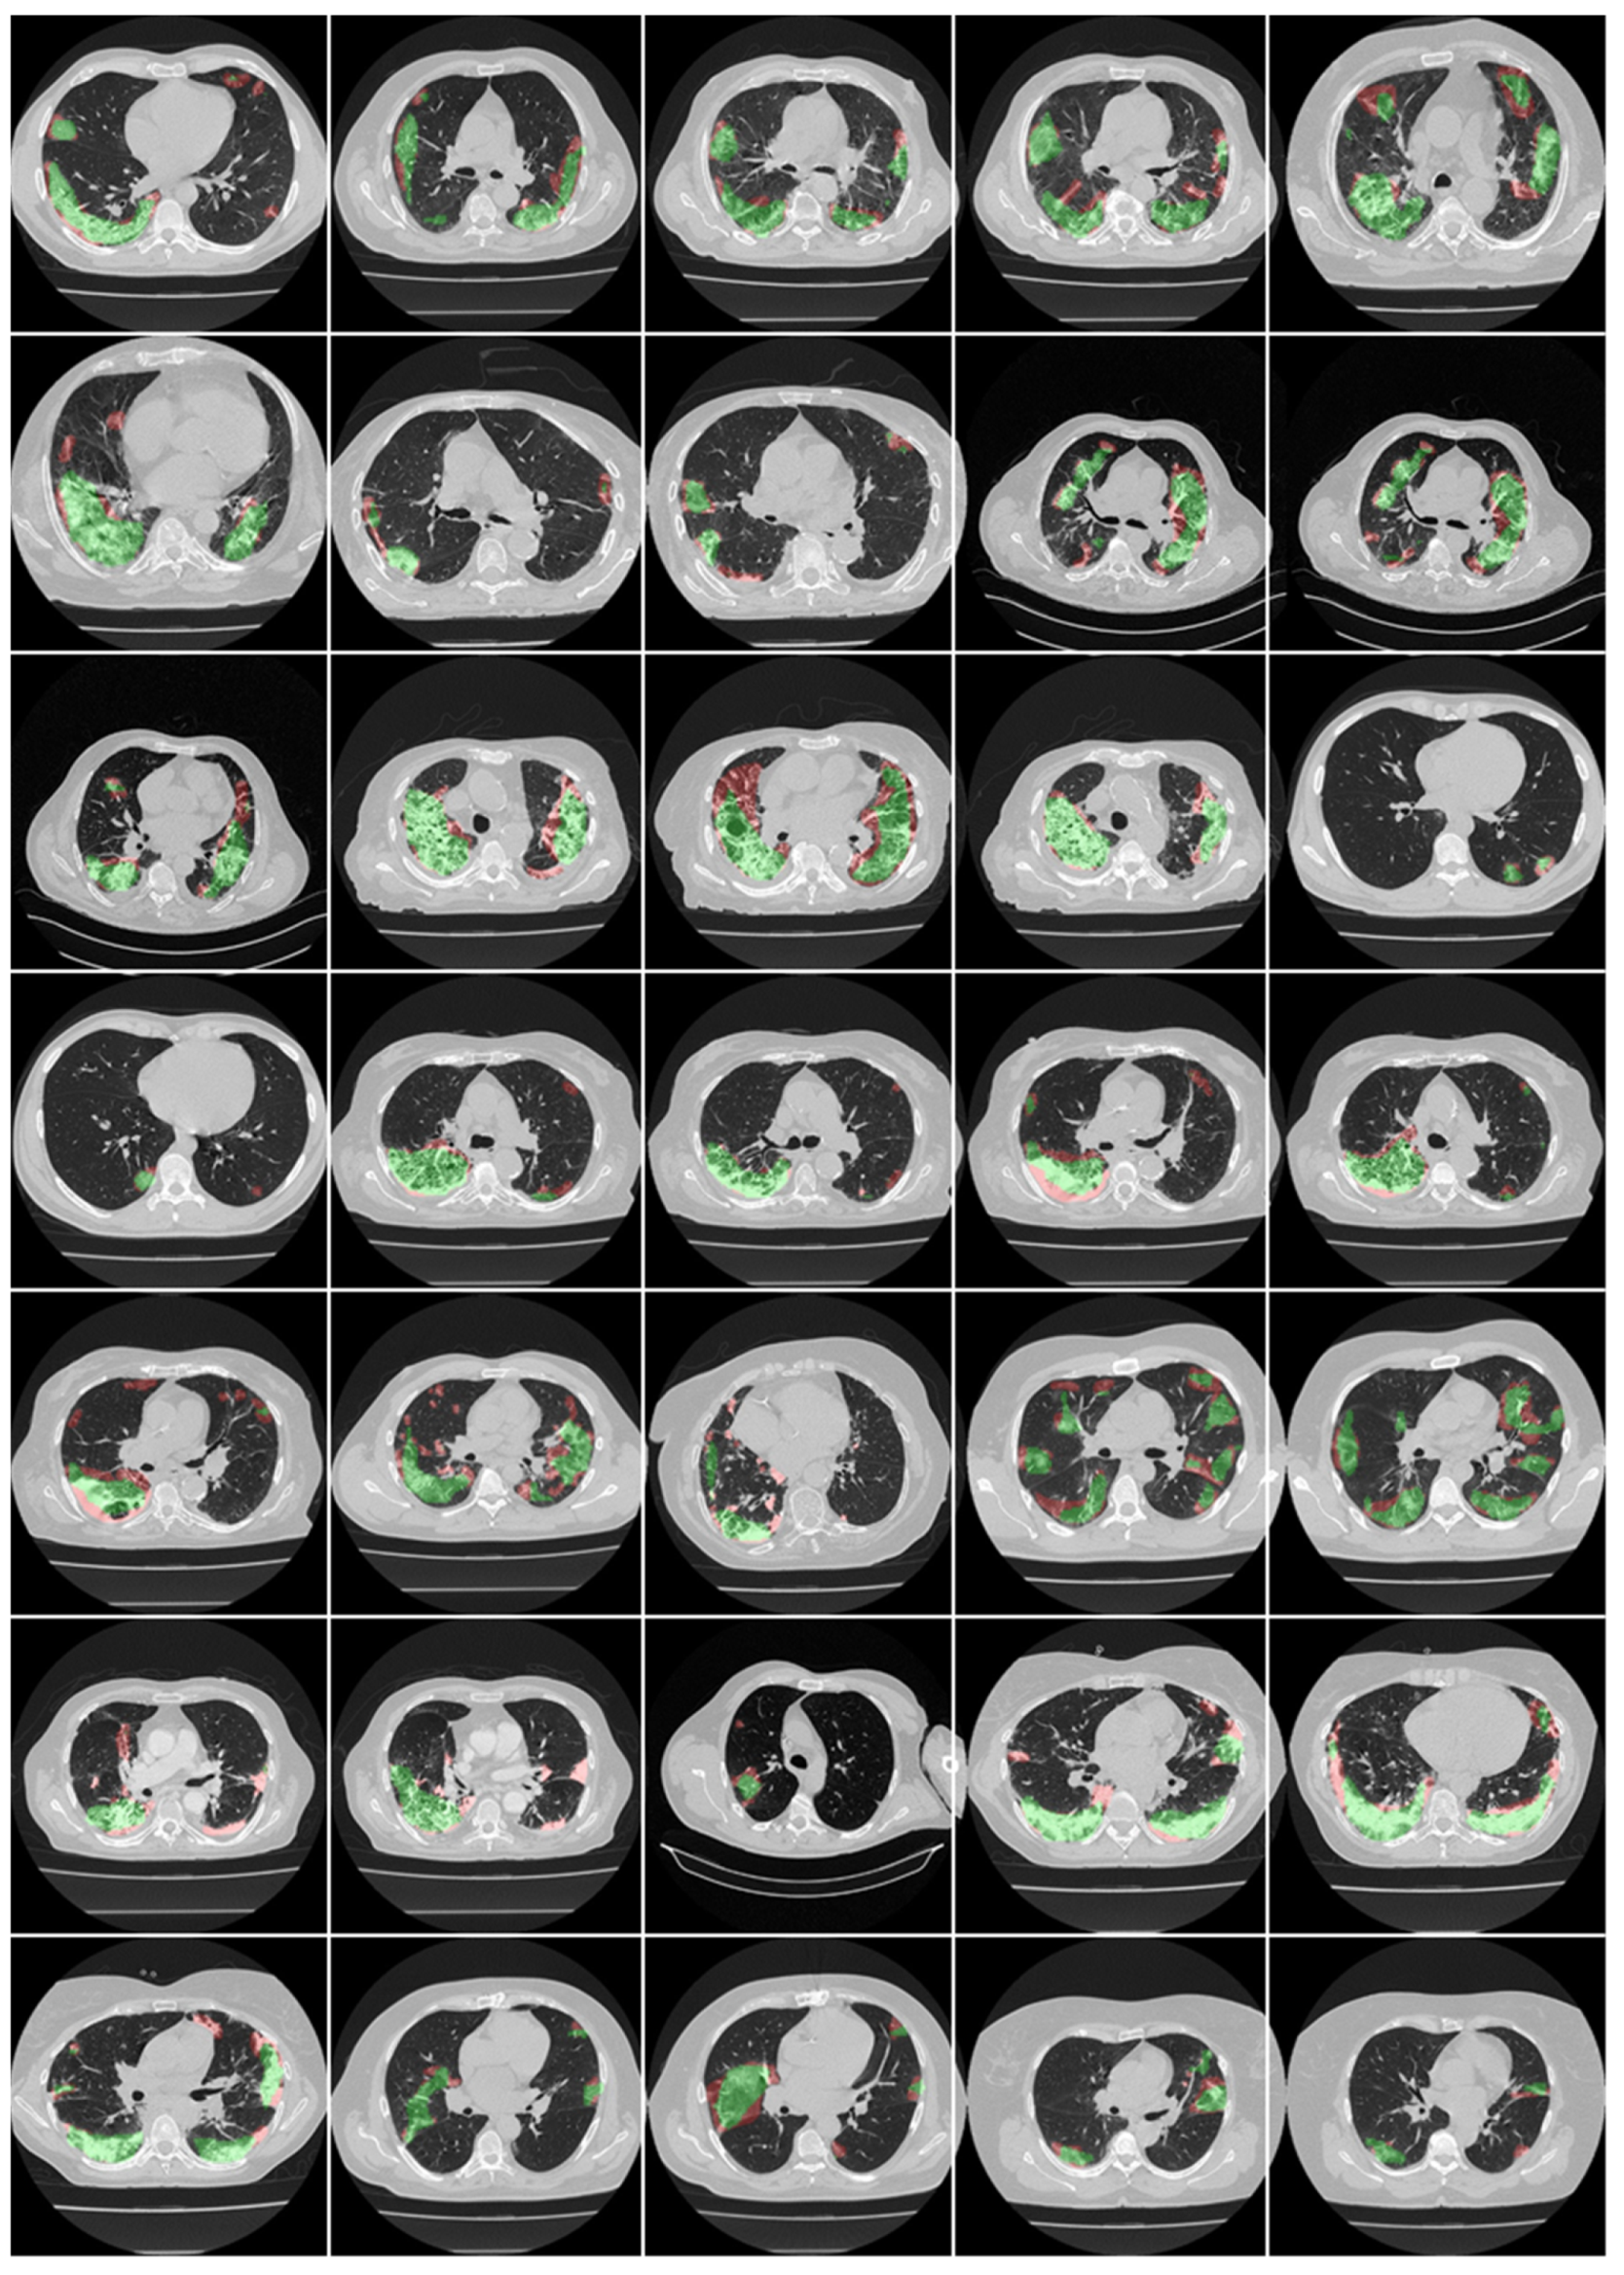

3.1. Results

3.2. Performance Evaluation